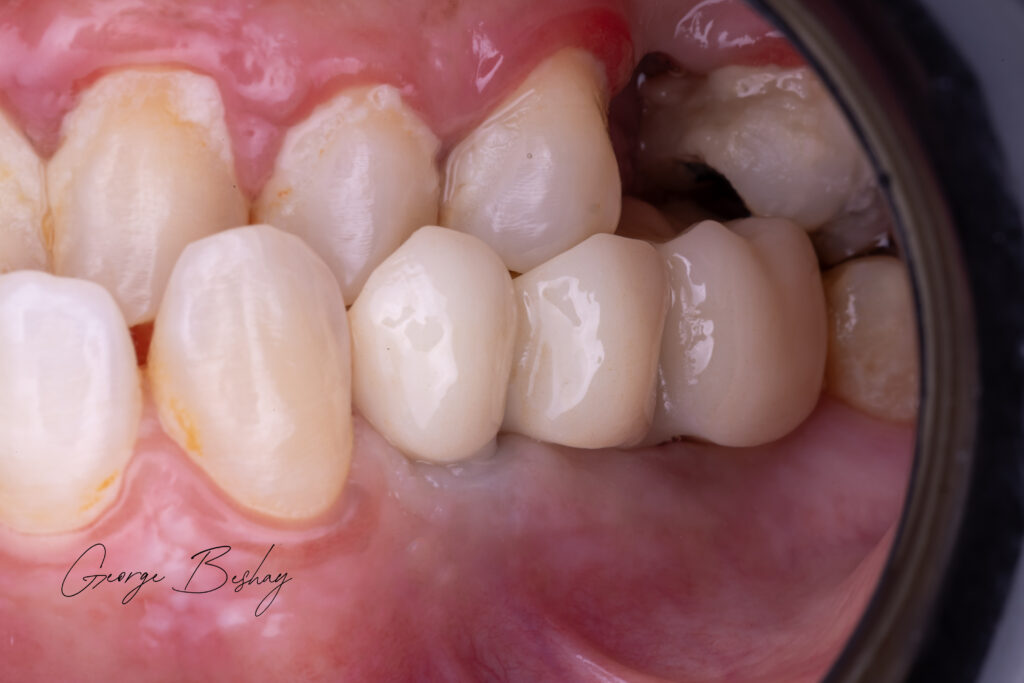

The patient needed posterior maxillary rehabilitation.

We placed a tilted implant, engaging available native bone, and restored the case with angled MUAs and a carefully planned distal cantilever to restore the molar.